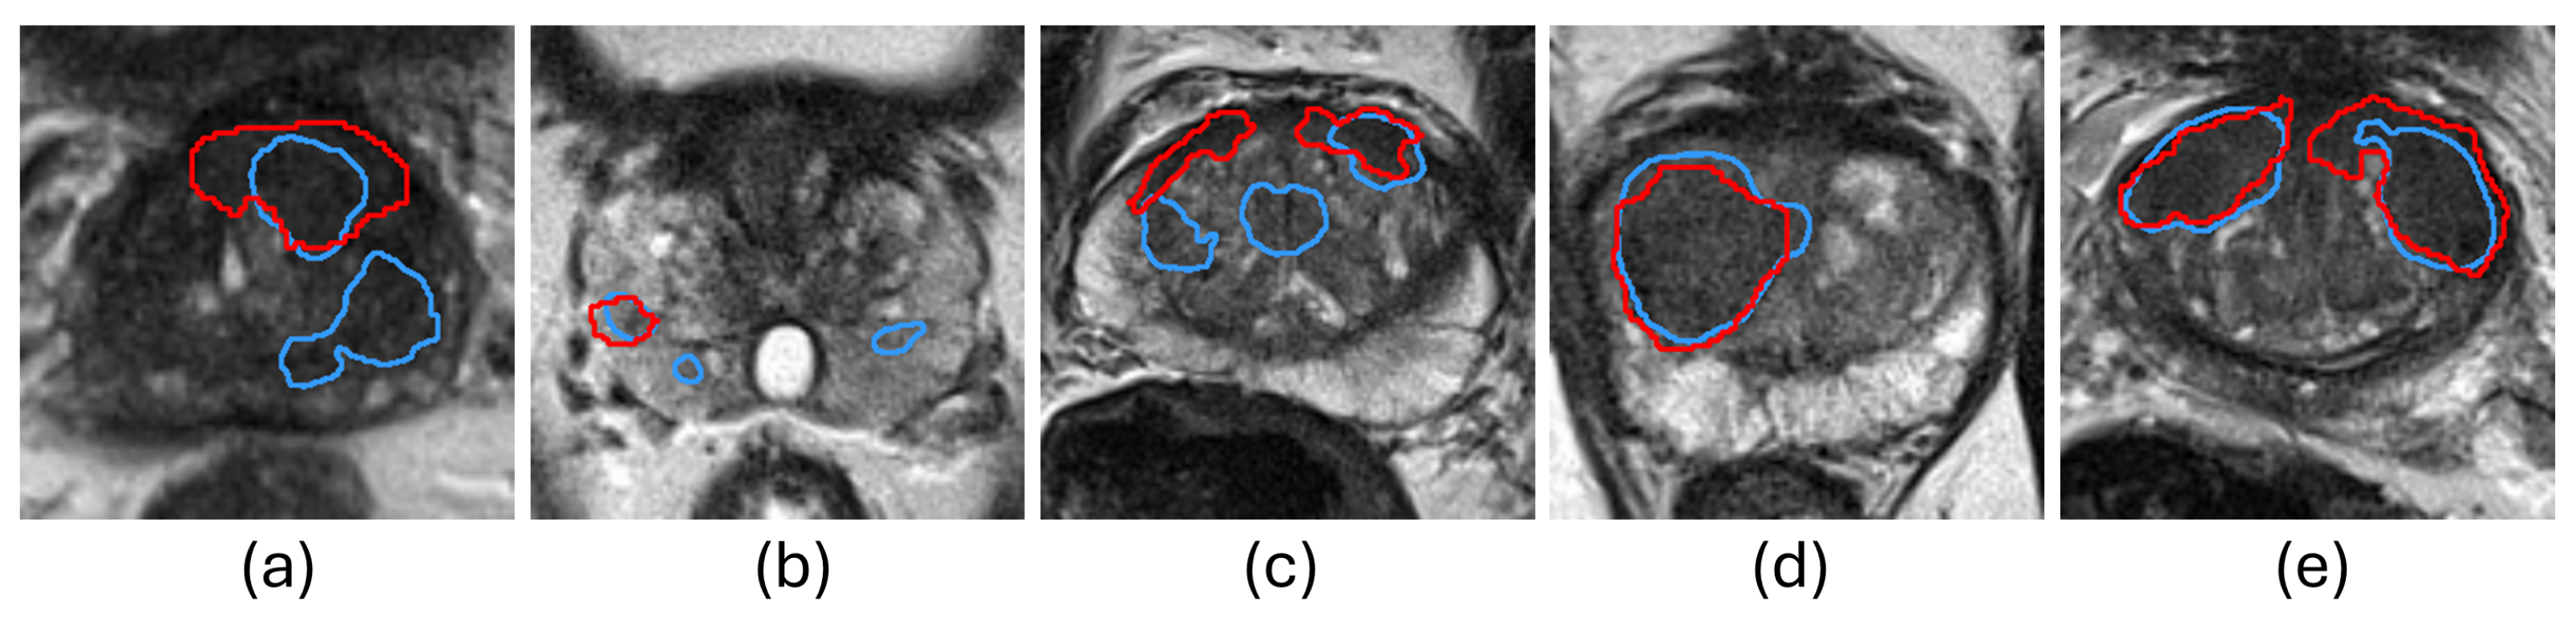

5.1.3. Lesion-Level Analysis